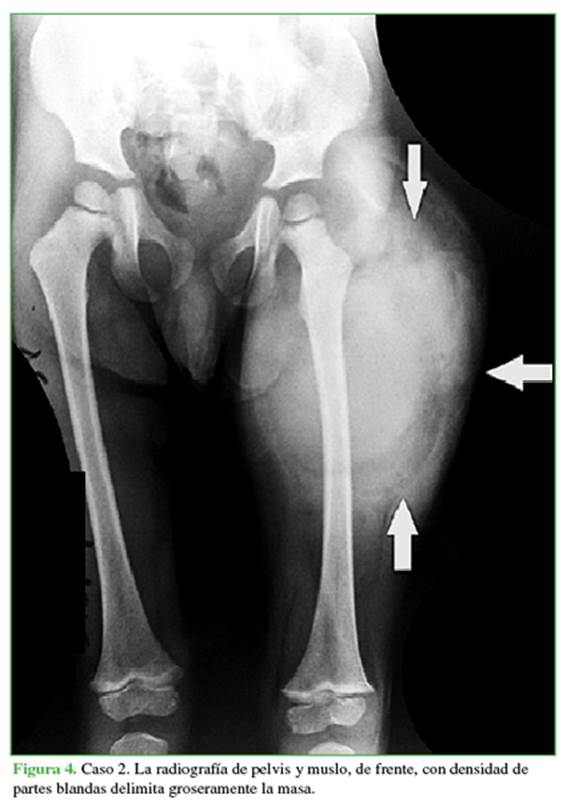

Cuando acude un paciente con estas características, habitualmente se solicitan estudios por imágenes. Las radiografías simples con densidad de partes blandas no son de gran utilidad, salvo para delimitar groseramente la masa (Figura 4).